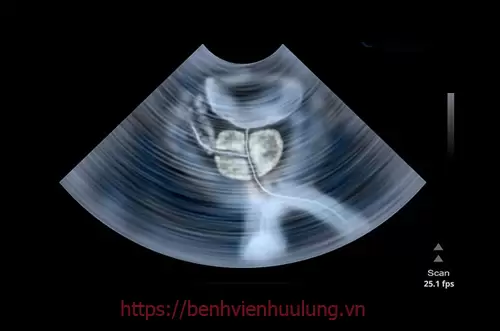

Phì đại tuyến tiền liệt (BPH) hay còn được gọi là u phì đại tiền liệt tuyến, u xơ tuyến tiền liệt, tăng sinh tiền liệt tuyến lành tính là một bệnh lý xảy ra do sự gia tăng nhanh chóng về kích thước tuyến tiền liệt, khi đó sẽ chèn ép vào bàng quang, niệu đạo và gây ra các rối loạn trong việc tiểu tiện.

Tùy vào mức độ nặng nhẹ của bệnh phì đại tuyến tiền liệt, có thể phân biệt được kích thước, trọng lượng của tuyến tiền liệt như:

- Ở mức độ nhẹ: Tuyến tiền liệt thường có kích thước từ 30g - 80g.

- Ở mức độ nặng: Tuyến tiền liệt có trọng lượng, kích thước lớn khoảng từ 100 - 200g.